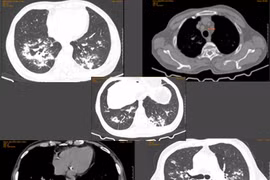

Xẹp phổi do lao được coi là “bản án chung thân” của biến chứng lao phổi. Nhờ tái tạo thành công đường thở bằng kỹ thuật nội soi tiên tiến, đánh bại "tam giác tử thần”, các bác sĩ đã làm “hồi sinh” phổi xẹp cho bệnh nhân lao.

Nhờ tái tạo thành công đường thở bằng kỹ thuật nội soi tiên tiến, đánh bại "tam giác tử thần”, các bác sĩ đã làm “hồi sinh” phổi xẹp cho bệnh nhân lao.